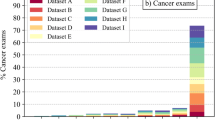

The distribution of risk scores for all mammograms, screen-detected cancers, and false positives is shown in Fig. 1. The cancer incidence in mammograms with low- and high-risk scores was 1.4/1000 and 13.6/1000, respectively. If mammograms with a risk score of 1 and 2 were to be excluded, 1829 (19.1%; 95% CI 18.3–19.9) normal exams could be removed, including 10 (5.3%; 95% CI 2.1–8.6) false positives, without missing a single cancer (Table 1). Half (53.0%, 95% CI 52.0–54.0) of the screen exams had low-risk scores (≤ 5). If these were to be excluded from screen reading performed by radiologists, seven (10.3%; 95% CI 3.1–17.5) cancers would have been missed, and 52 (27.8%; 95% CI 21.4–34.2) false positives would have been avoided. All seven cancers with low-risk scores were invasive (Table 2), of which three were small (≤ 7 mm), low-grade invasive tubular carcinomas, i.e. tumours with excellent prognosis [19]. On the other hand, three cancers, two ductal and one lobular type, were large (20 mm), one of which was histologic grade 3, i.e. of less-favourable prognosis. The radiologists’ consensus panel judged all cancers, except one, to be clearly visible (Fig. 2). The latter was a 20-mm-large mammographically occult invasive ductal carcinoma that was recalled due to an imaging finding of a pathologically enlarged lymph node. Six of the cancers had a radiographic appearance of a spiculated mass. All, except one, of the women with AI-missed cancers had dense breasts (Breast Imaging Reporting and Data System-category C and D [21]).

As shown in Table 2, the most common type of screen-detected cancers was an invasive ductal carcinoma. The majority of mammograms with invasive ductal carcinomas were classified with high-risk scores. Notably, 10 out of 11 mammograms with invasive lobular cancers, a cancer type that is known to sometimes have a subtle radiographic appearance, were also classified with high-risk scores. Furthermore, high-risk scores were assigned to all cancers with calcifications as the dominating radiographic feature (Fig. 3). The majority (10/14) of these were ductal carcinoma in situ. Finally, all but one of the seven high-grade cancers had a risk score of 10.

The present study aimed to assess whether AI could identify normal exams in mammography screening. We found that with AI, every fifth mammogram could be excluded from screen reading performed by radiologists without missing cancers, and at the same time a number of false positives could be avoided. Consequently, radiologists’ workload and costs related to screen reading and false positives could potentially be reduced. Considering that the double-reading procedure is practiced in many screening programmes, especially in Europe [22], the saving could be substantial. In this specific Swedish screening setting with low recall rates (2.6%), the reduction of false positives was small. It is fair to assume that the reduction of false positives could be greater in a setting where the recall rates are higher, such as in the USA [23, 24]. The majority of the false-positive mammograms had high-risk scores, reflecting the fact that both human readers and AI found suspicious features in the same image.

The size of the reduction of screen exams from radiologists’ reading also depends on whether the trade-off in terms of a slight reduction of sensitivity could be considered acceptable. If we would exclude mammograms with low-risk scores (half of all screen exams), 28% of the false positives could be avoided. This does not seem acceptable since 10% of the cancers would have been missed. Since half of the AI-missed cancers were indolent cancers, i.e. low-grade invasive tubular cancers, the trade-off might still be considered. We have to keep in mind that the results are point estimates with mostly broad confidence intervals; the percentage of missed cancers may be as few as 3% and as many as 18%. The magnitude of normal exams identified in this study was similar to the results presented by Rodriguez-Ruiz et al using the same AI system, but on a study population with both clinical and screening mammography exams [25], and by Yala et al using a different AI system than the one used in this study, on a large screening data set [26].